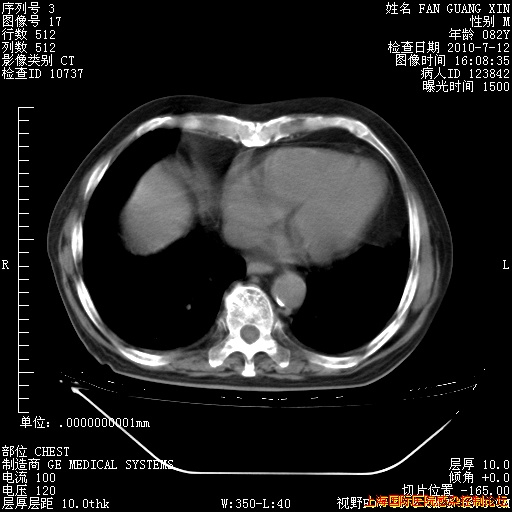

今天复查CT

今天CT

整整相隔30天的肺部CT好像有所好转啊。甲强龙减量第3天,需要观察体温。